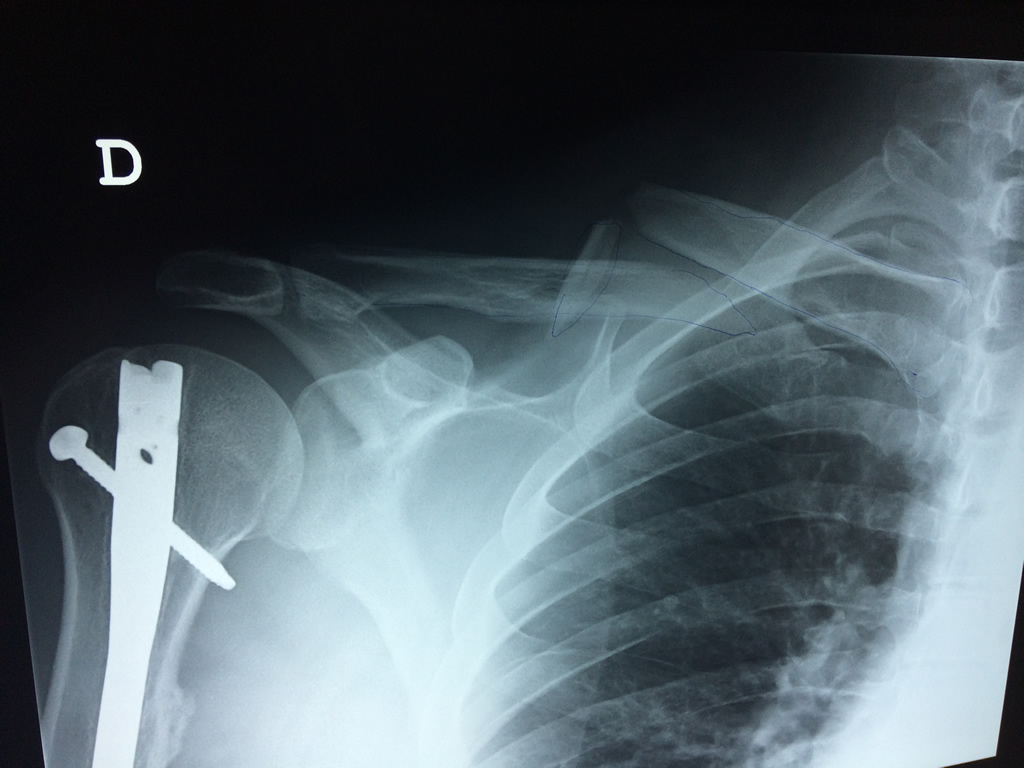

Cirugías de Calcaneo - Clavícula

La clavícula es un hueso largo, con forma de "S" itálica, situado en la parte anterosuperior del tórax. Junto con la escápula forman la cintura escapular. Se puede palpar por toda su longitud y se extiende del esternón al acromion de la escápula, siguiendo una dirección oblicua lateral y posterior.